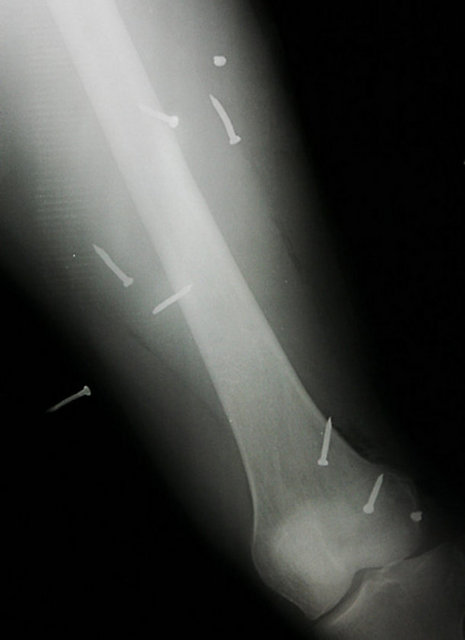

"Özellikle havaalanlarındaki girişlerde iki tür cihazı da görebiliriz. Eşyaların geçirildiği X-Ray cihazında X ışınları kullanılarak görüntüleme yapılır. Çantaların içinde ne olduğu X ışınları ile görüntülenir. Burada uygulanan X ışınlarının eşyalara bir zararı yoktur, birikmez, eşyalarda radyasyon kirliliği yapmaz. Bu cihazların çevresi X ışınlarının insanlara zarar vermemesi için kurşun paravanlarla kaplıdır."